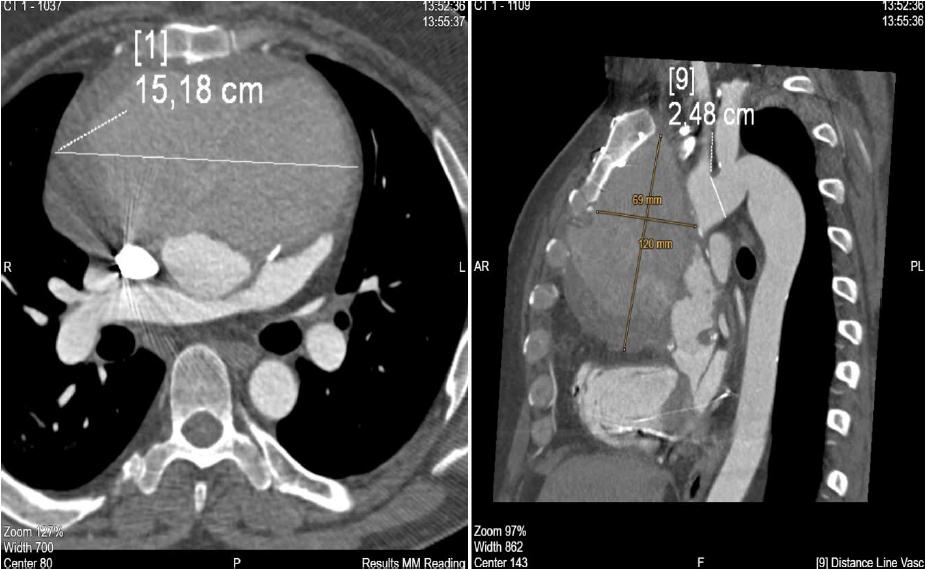

TAFA was diagnosed by CT (Figure 1) and completed with an echocardiogram to evaluate every case correctly.

CT scan of aortic pseudoaneurysm.